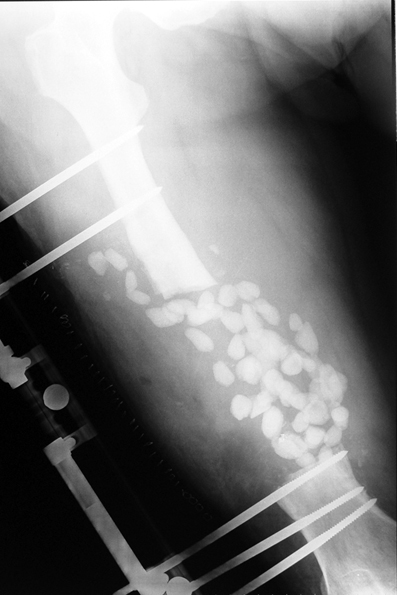

Kronik osteomiyelit, kemik ve yumuşak dokularda nekroza yol açar. Ölü kemik, patojen mikroorganizmalara ev sahipliği yapan bir nidus oluşturur. Konağın savunma sistemleri, mikroorganizmalarla baş etmek için sıklıkla optimal koşullarda değildir. Dolaşım bozukluğu yüzünden enfeksiyon bölgesine antibiyotikler yeterince ulaşamaz. Bu nedenle ölü dokuların ortamdan tamamen uzaklaştırılması gerekir (radikal debridman).

Uygun radikal debridman tüm nekrotik kemik ve yumuşak dokuların çıkartılmasını gerektirir, ve sıklıkla uzuvda instabiliteye neden olur. Kalan kemik ve yumuşak doku defektinin bir şekilde fiksasyonu ve rekonstrüksiyonu gereklidir. İlizarov’un ortaya koyduğu distraksiyon osteogenezi yöntemi, kaynamanın elde edilmesi, deformitenin düzeltilmesi, bacak boy eşitsizliğinin giderilmesi ve segmental defektlerin rekonstrükte edilmesi için başarıyla kullanılmaktadır.